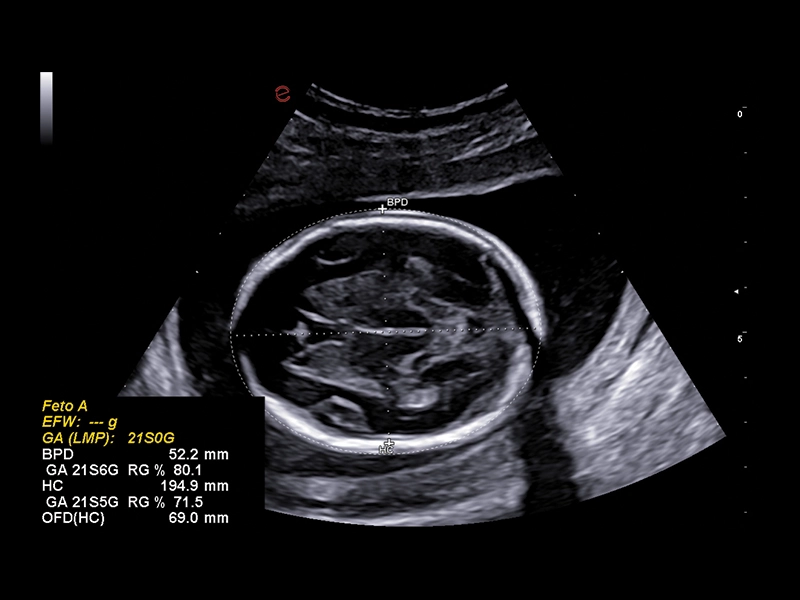

MyLab™C25 - AUTO OB

MyLab™C25 - AUTO OB